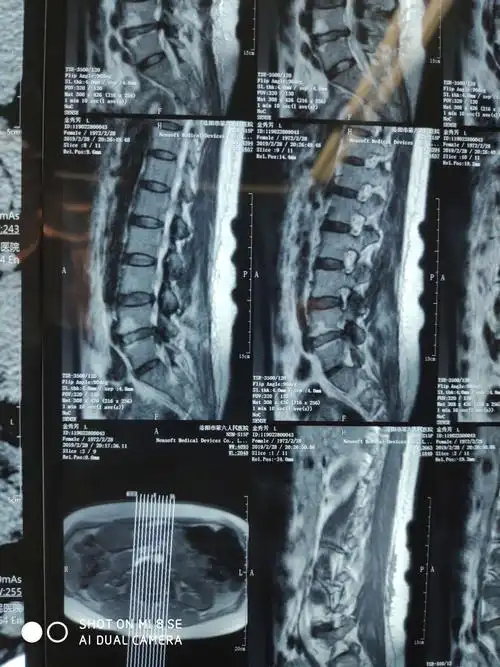

一例脱垂型腰间盘突出症的经椎间孔镜手术